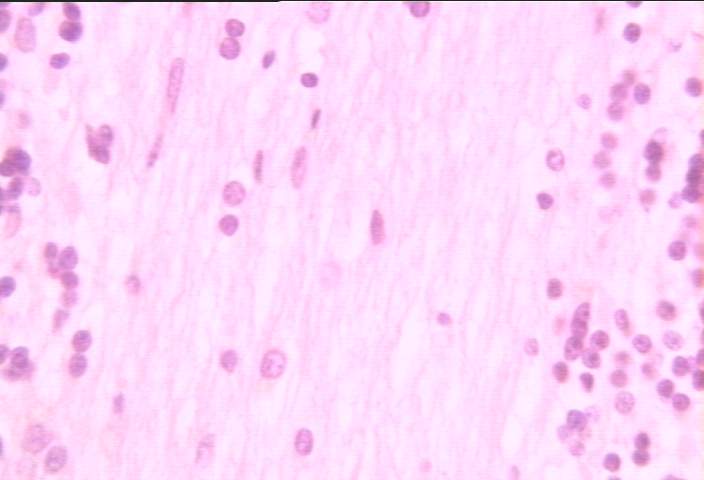

切片位置:小腦髓質

切片倍率:400x

染色方式:h&e stain

高倍率 (400x) 常規染色之小腦髓質 (medulla),呈淡染色夾於顆粒層 (granular layer) 之間,分布其間之細胞核為神經膠細胞 (neuroglia) 所有。